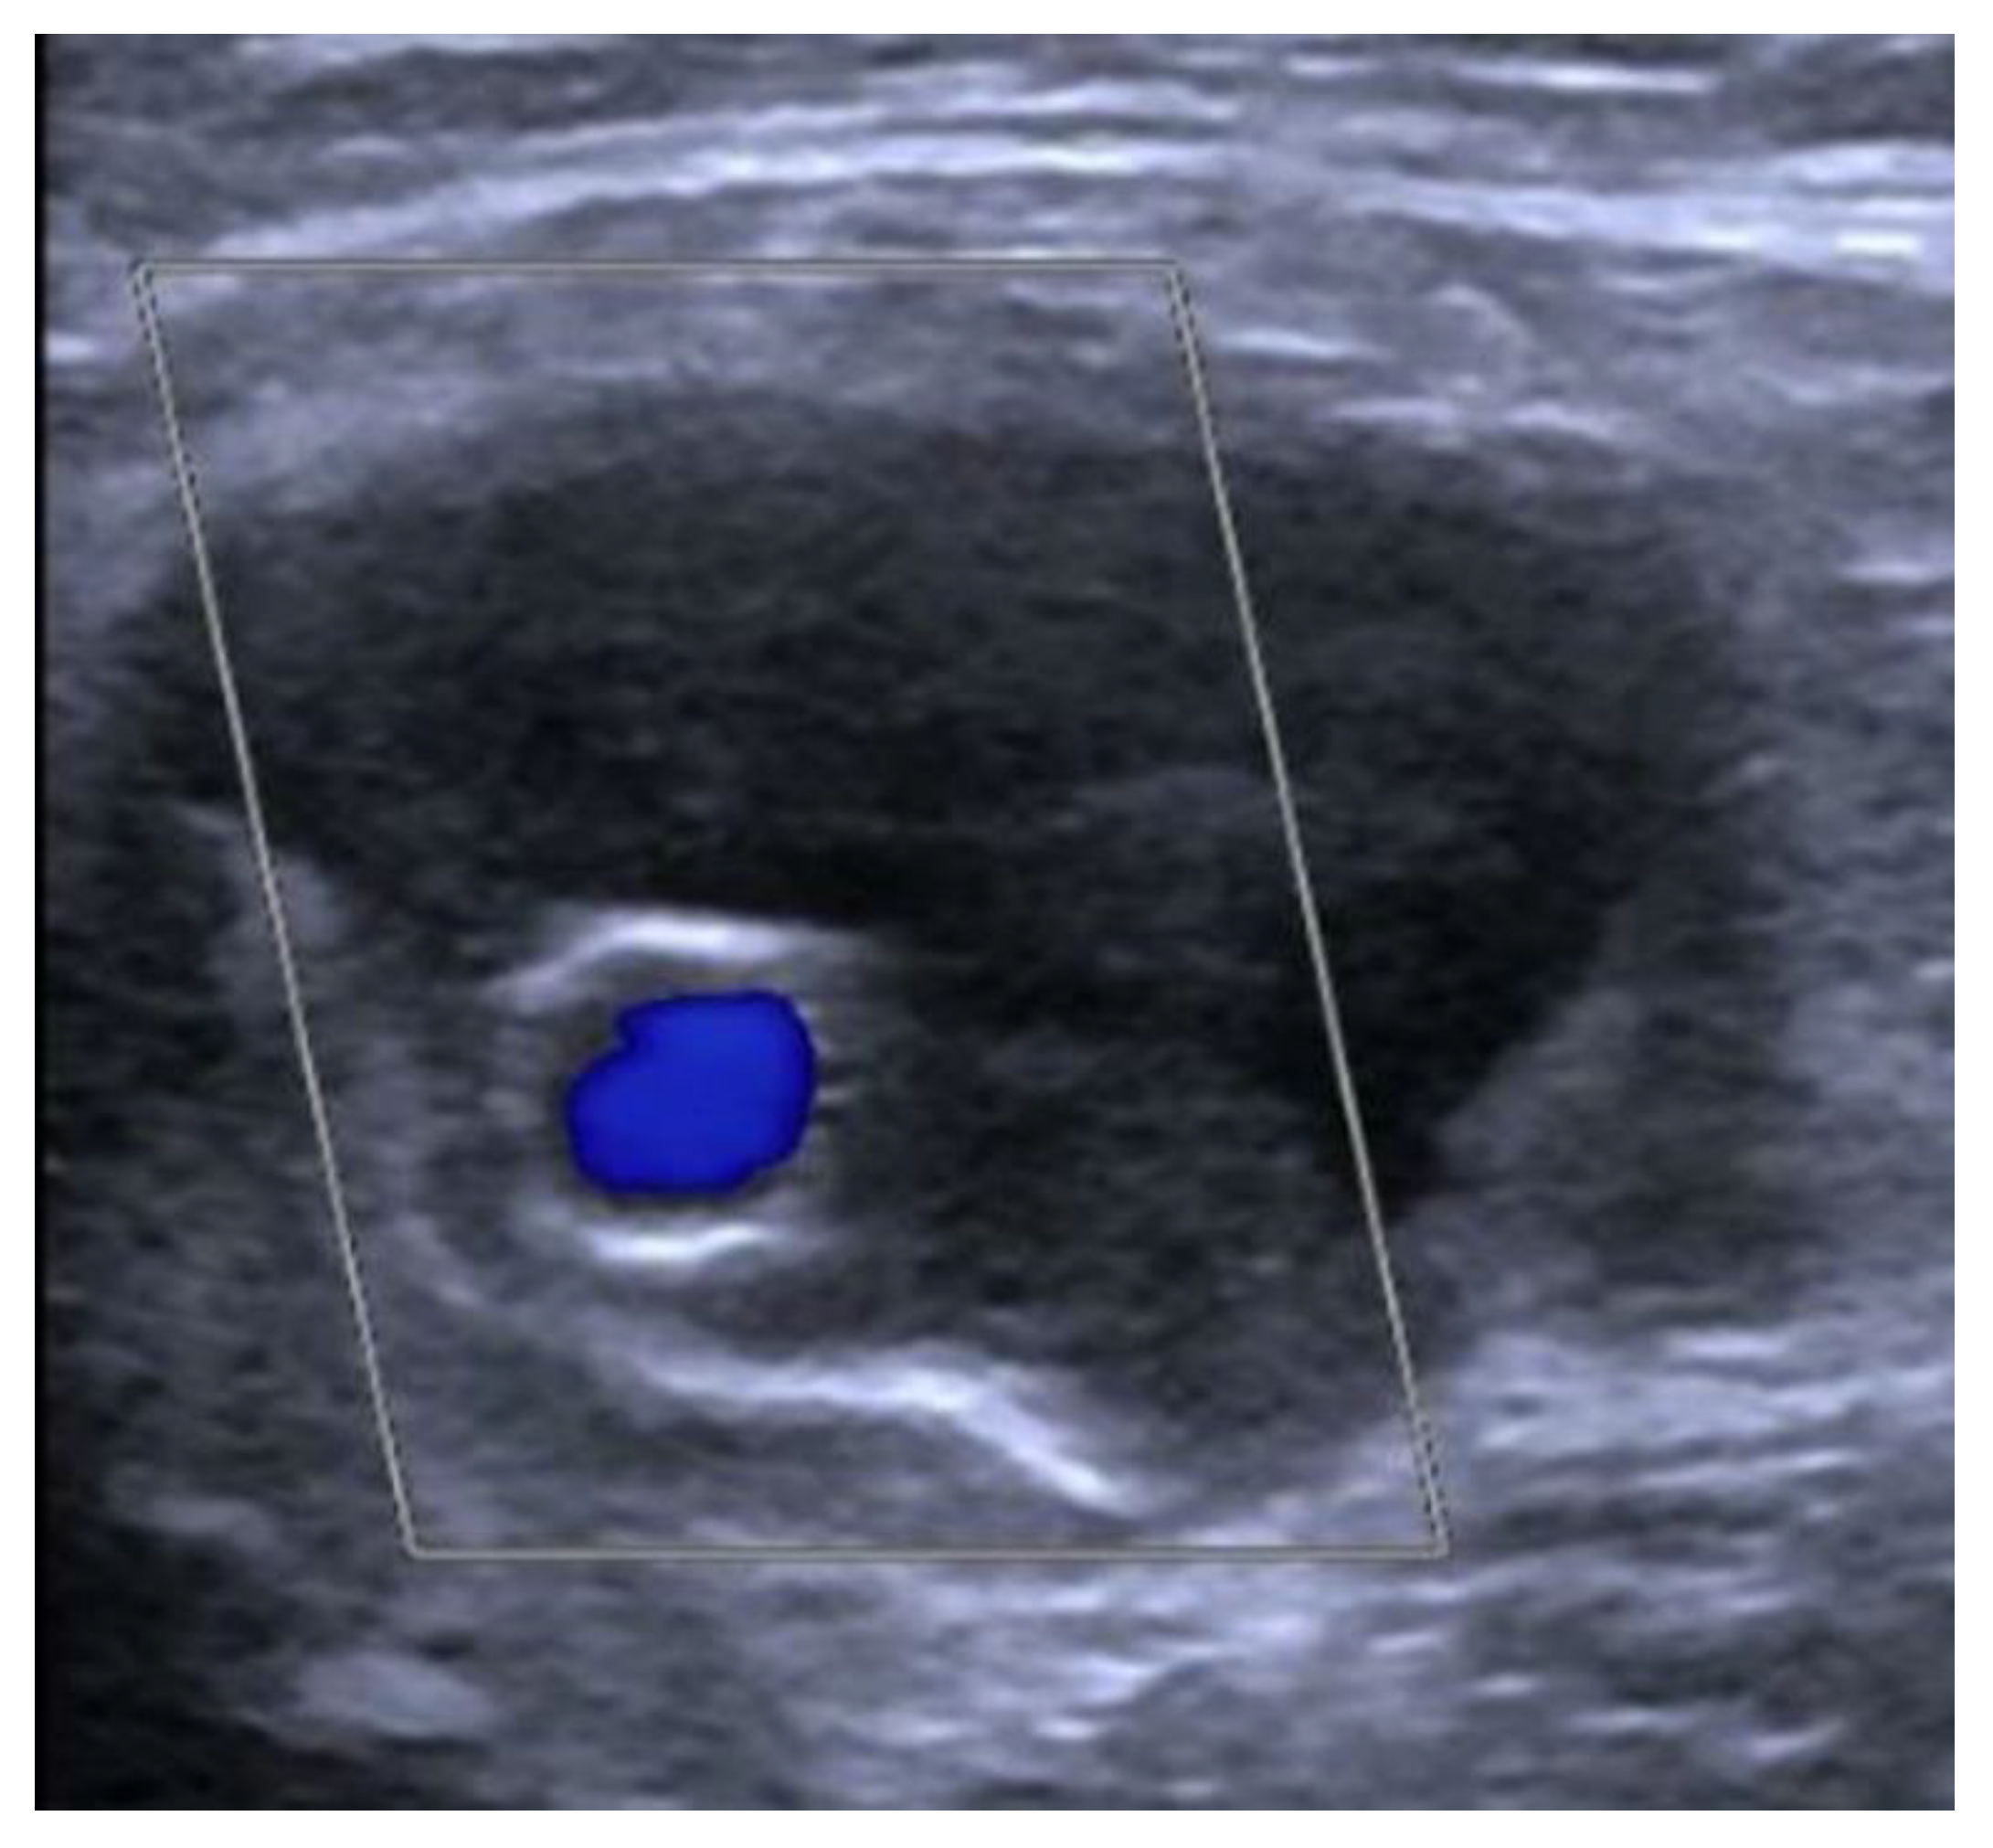

Figure 5. Color Doppler Ultrasound: patent stent graft inside the excluded distal anastomotic PA.

The completion arteriogram showed the resolution of the occlusion with the direct and increased distal flow without any complications (Figure 4a–d). Successful haemostasis with FemoSeal (Terumo Europe) was obtained. The stent graft has adapted perfectly to the morphology of the lesions to be treated. The popliteal artery was reperfused to the third proximal through the collateral vessel; the vessel did not show significant atheromatous plaques. After treatment, the patient underwent therapy with clopidogrel (75 mg) + ASA (100 mg) for 2 months; next with only ASA (100 mg). Color Doppler Ultrasound after 1-3-6-9-12 months from the procedure showed patent self-expanding stent graft inside the excluded PA (Figure 5).